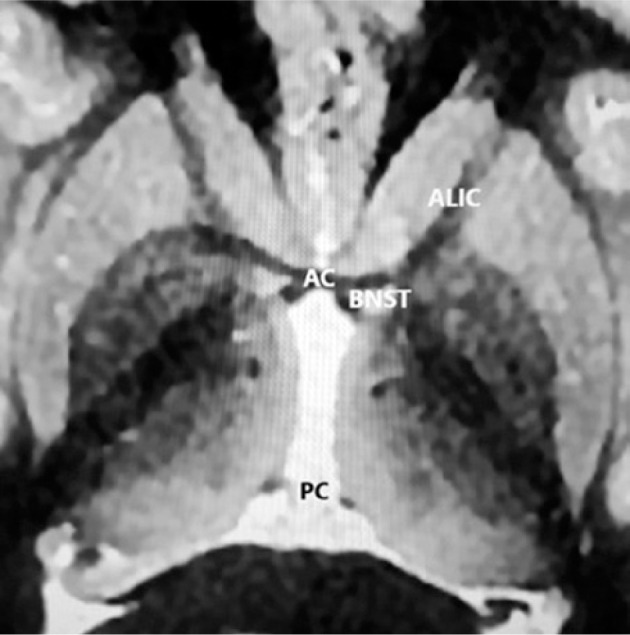

Purpose: The bed nucleus of the stria terminalis (BNST) is a tiny nucleus connected by a bundle of axons with the amygdala. The BNST acts as a relay center, coordinating autonomic, limbic, behavioral, neuroendocrine, and motor functions. It plays a key role in anxiety and anxiety-related disorders. This review presents clinical outcomes of deep brain stimulation (DBS) of the BNST in treatment-resistant obsessive-compulsive disorder (trOCD) and treatment-resistant depression (TRD).